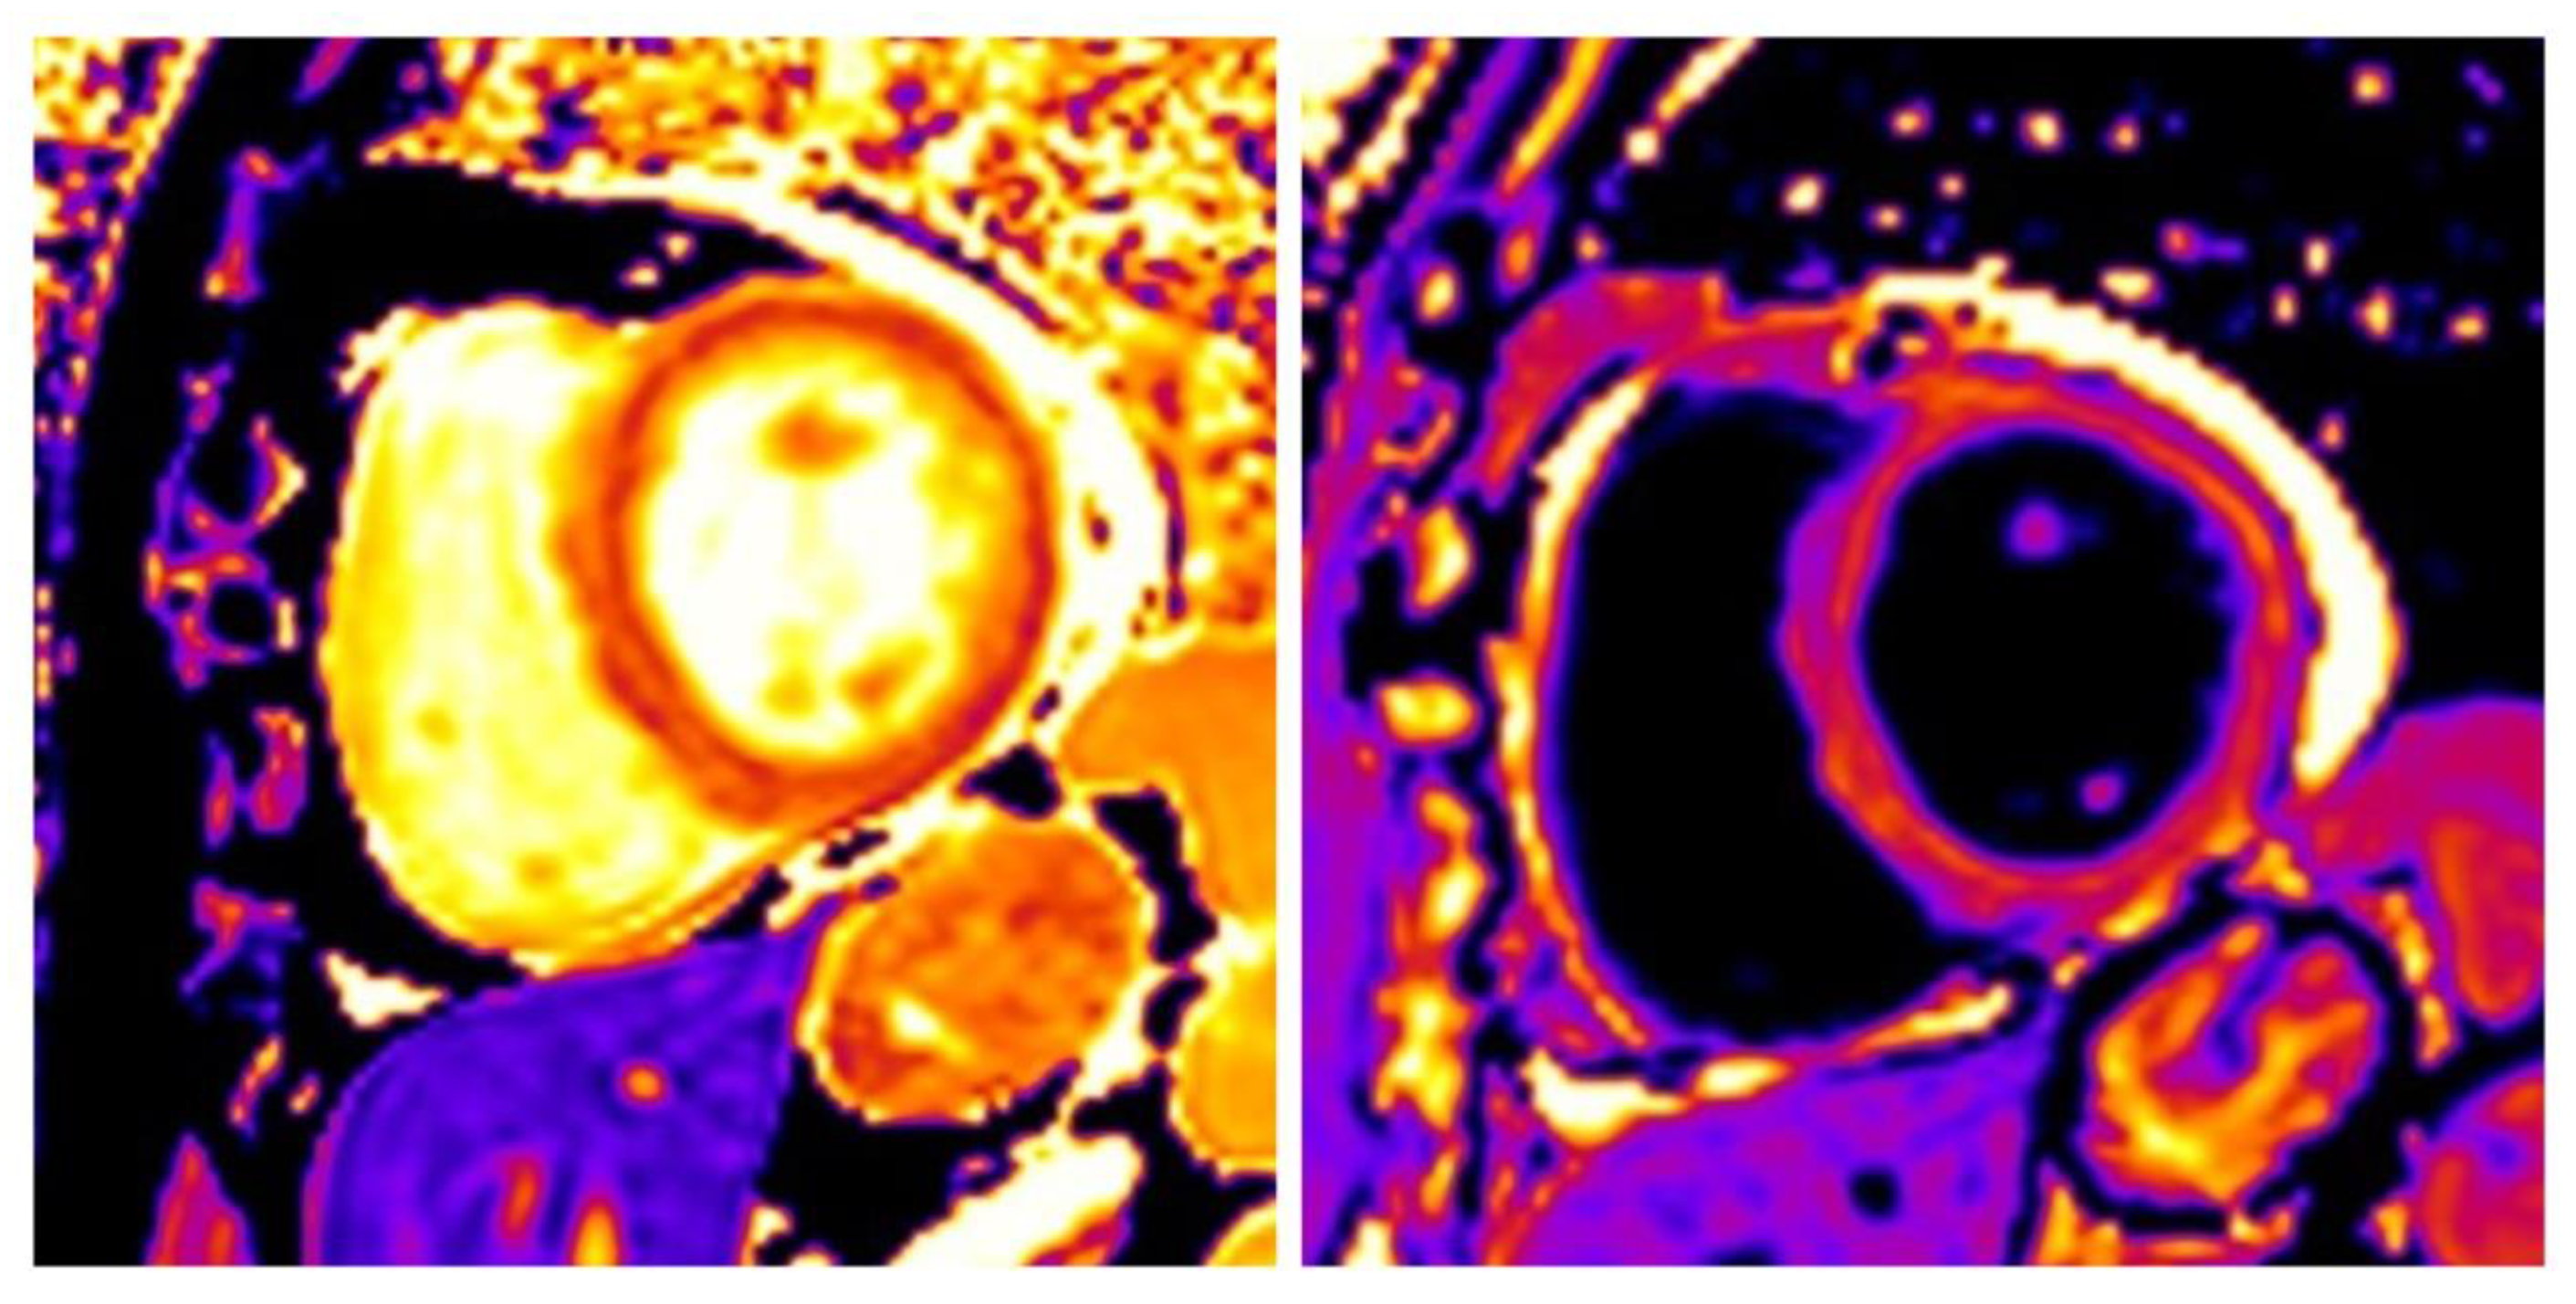

3.3. Hypertrophic Cardiomyopathy